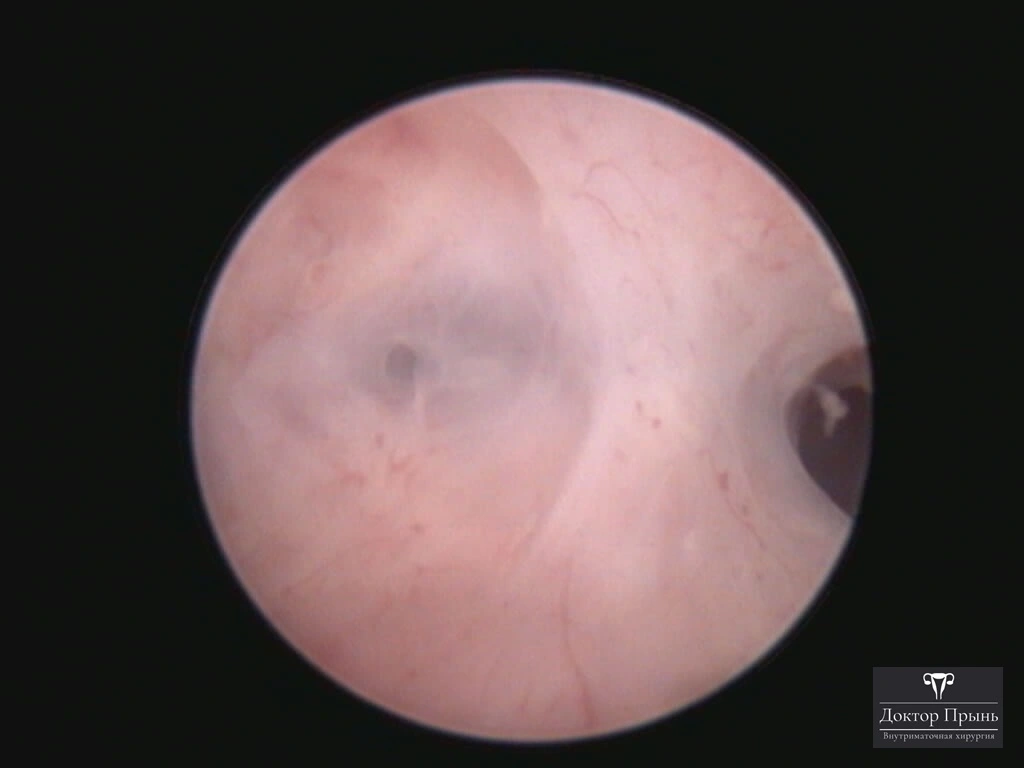

Фотогалерея

Синехии, рассечённые Прынь Д.В.

Гистероскопия позволяет не только увидеть спайки, но и сразу вылечить, т.е. рассечь их. Большинству пациенток подойдёт офисная гистероскопия без наркоза и госпитализации. Среднее время операции 15 минут. Иногда требуется 2-4 операции, чтобы восстановить полость матки.

Крайне важен способ разделения спаек. Если это холодный инструмент, например, ножницы, то вероятность рецидива низкая. Плюс не повреждается нормальный эндометрий. Если рассекают горячей электропетлёй, то, наоборот, риск рецидива высокий и можно обжечь эндометрий.